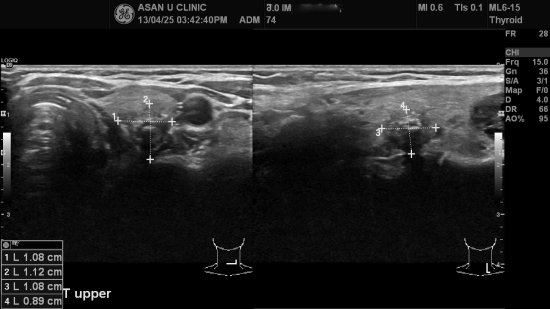

2012년 12월에 유방암 진단받으신 분으로 1월에 유방암

수술을 받으셨으나

수술후 PET scan상 갑상선에 의심소견있어

본원에서 갑상선초음파 및 침생검으로 갑상선 유두암 진단받으셨습니다.